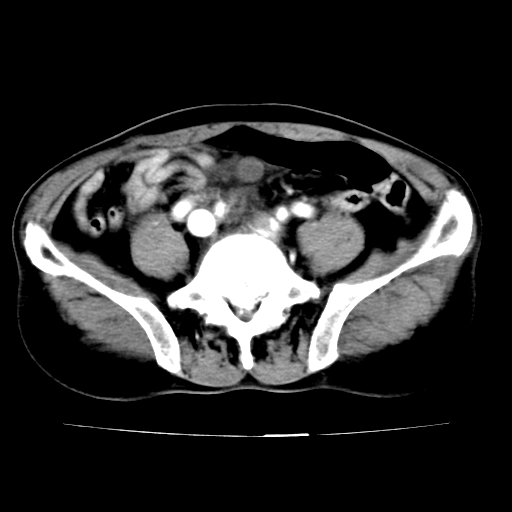

腹总动脉瘤伴附壁血栓形成累及髂总动脉

腹总动脉瘤伴附壁血栓形成累积髂总动脉 支持

腹主动脉分叉处真性动脉瘤,附壁血栓形成。

各位老师注意到下腔静脉的充盈缺损了吗?注意到动静脉漏了吗?

腹总动脉瘤伴附壁血栓形成累及髂总动脉,看起来好像有动静脉瘘,但我认为是扫描时象造成的假象。

当时是扫描的标准动脉期,可是下腔静脉与腹主动脉同步强化且幅度一致。所以我想动静脉瘘是存在的。